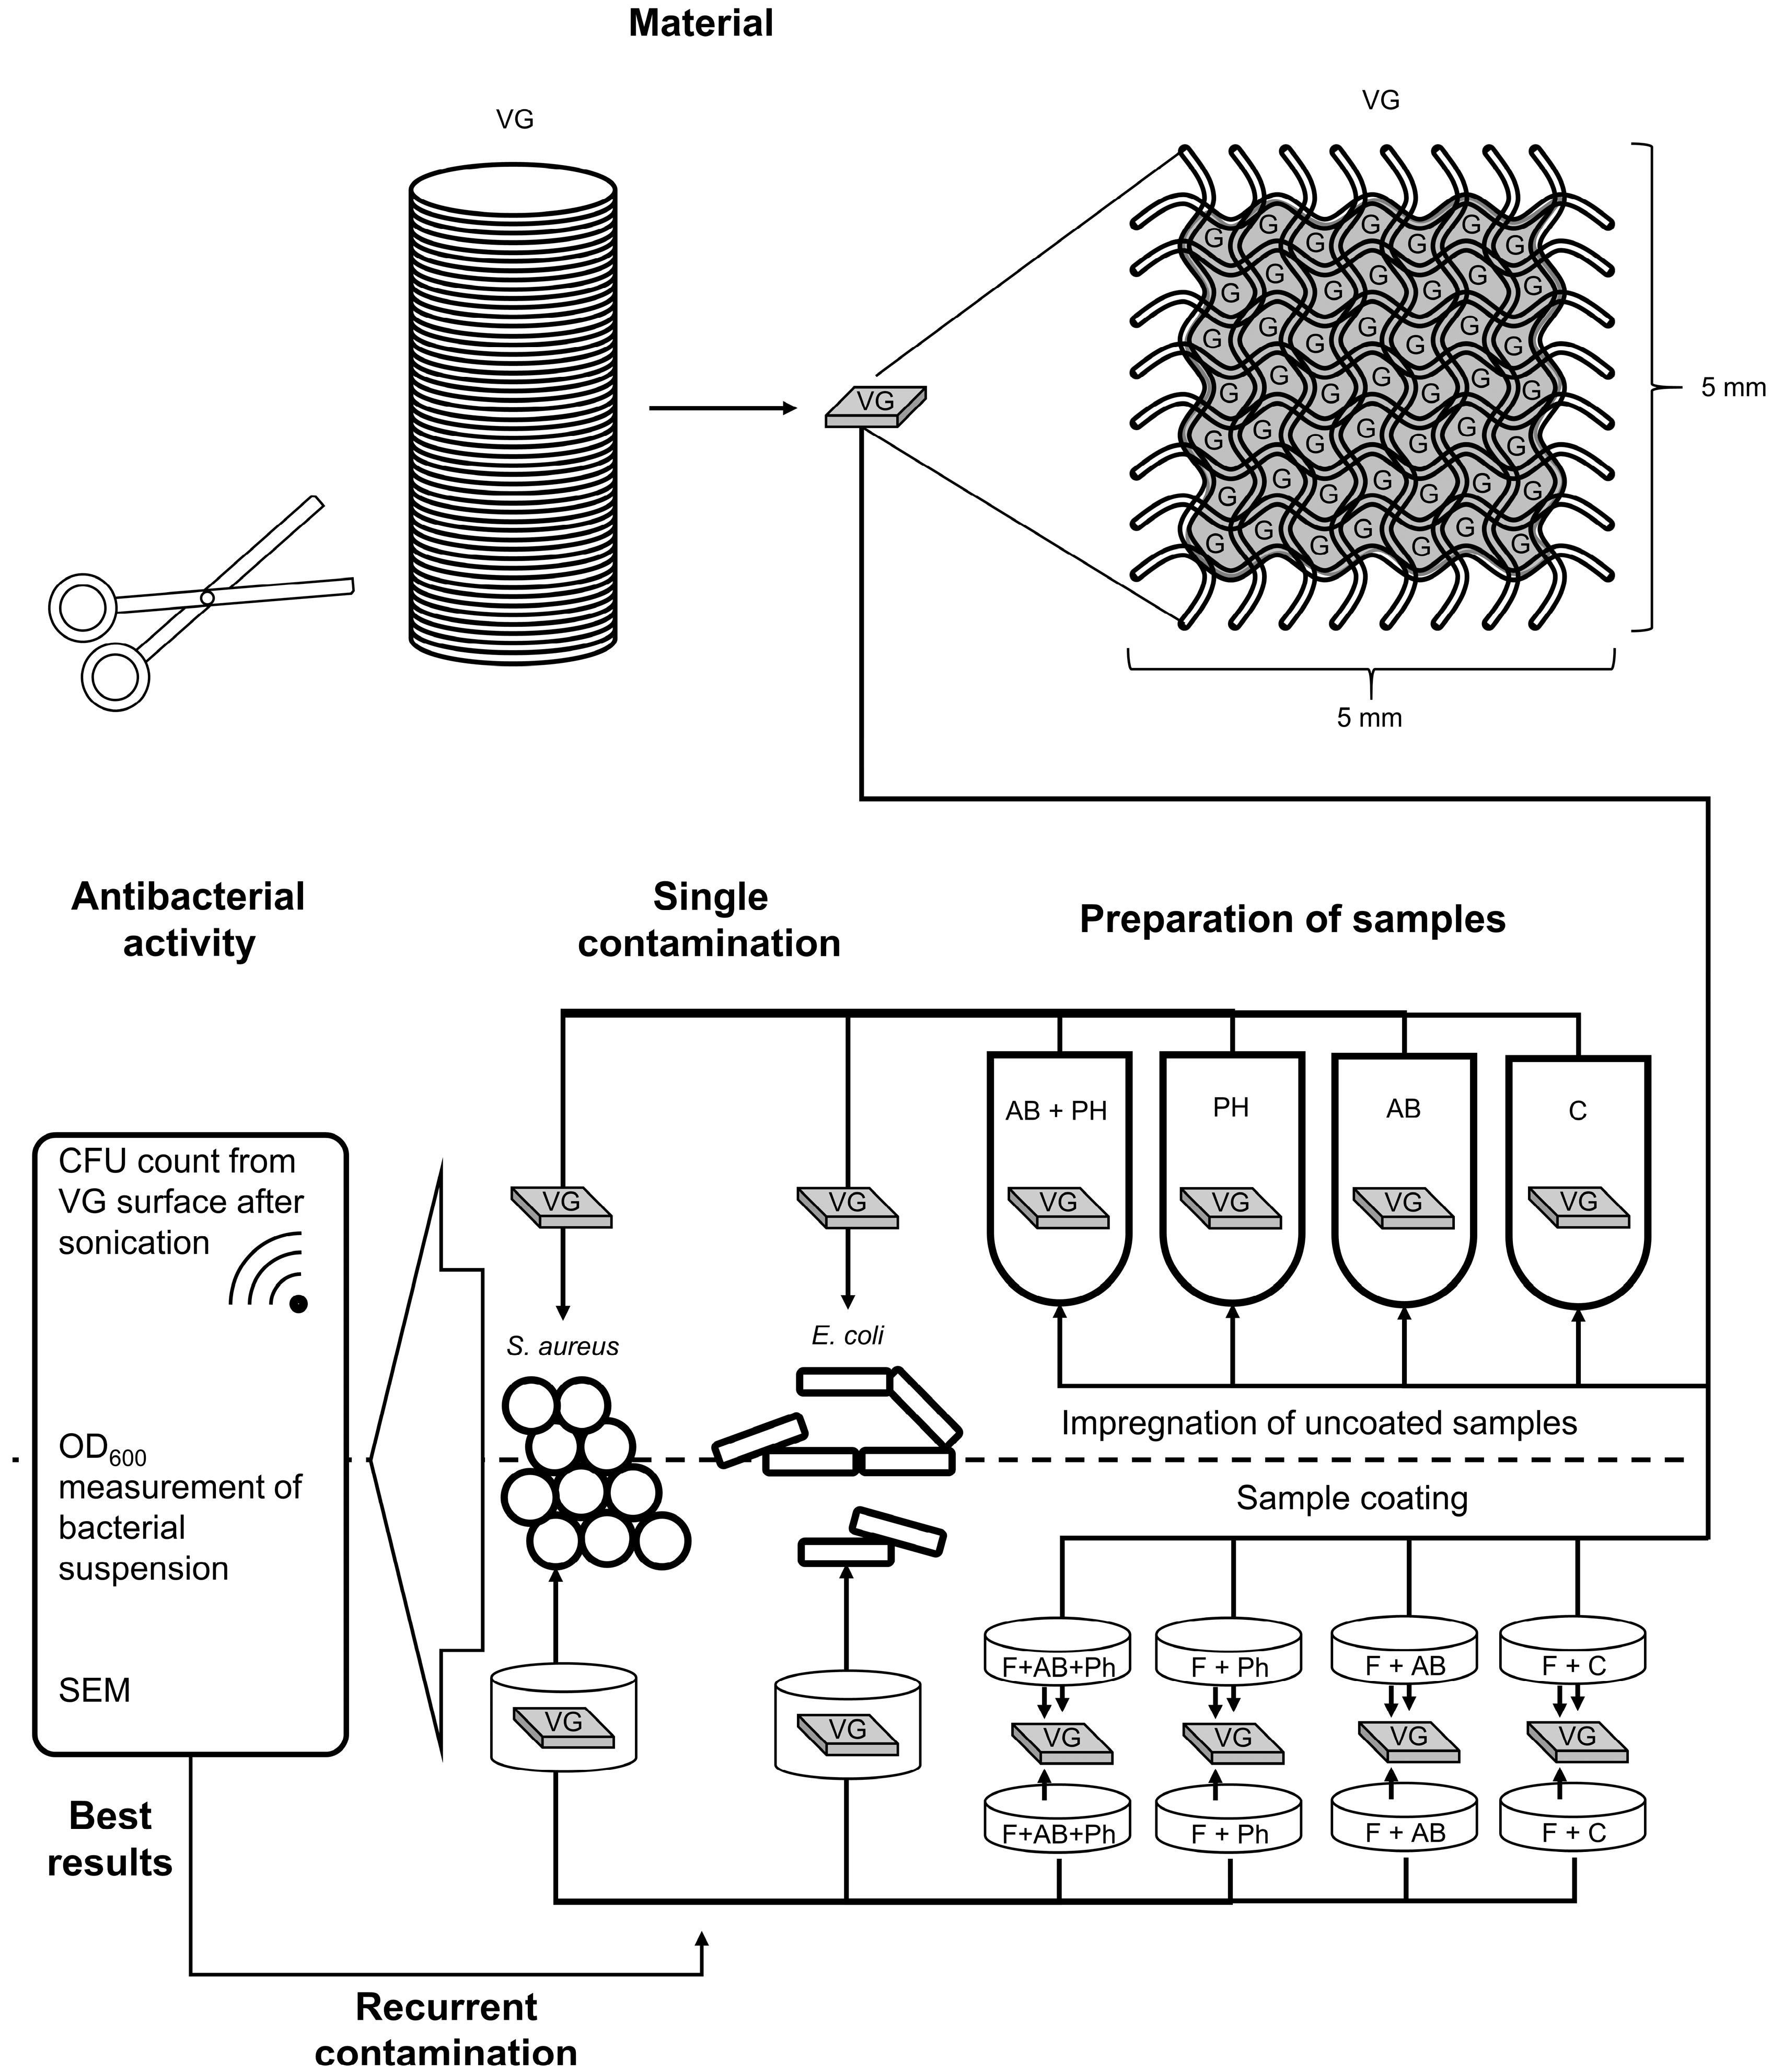

2. Results

2.1. Surface Coating of the Grafts

2.2. Antibacterial Loads of Graft Samples

2.2.1. Uncoated Grafts

2.2.2. Coated Grafts

2.3. Antibacterial Activity against Single Contamination

4.2. Methods

4.2.2. Impregnation of Uncoated Samples

4.2.3. Preparation of Coated Samples

4.2.4. Processing of Samples—Antibacterial Activity against Single Contamination

4.2.6. Processing of Samples—Antibacterial Activity against Recurrent Contamination